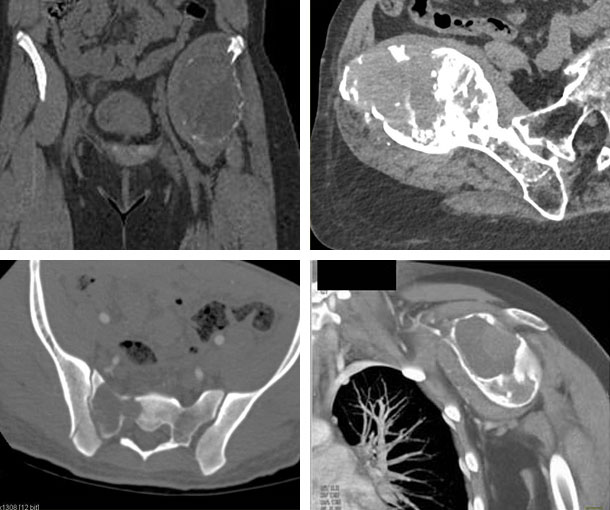

Giant Cell Tumor CT Findings

- Most common in long bones

- Lytic lesion centered in the epiphysis

- Lesions begin in the intramedullary region of the major long bones

- Typically develop near the articular cartilage

- Osteolytic destruction

- Bone shells may be complete or incomplete

- Circumscribed borders

- Uniform cystic density

- No calcification

- May extend into the soft tissue and form soft tissue masses as the tumor progresses

- More difficult to differentiate GCT from other osteolytic processes on CT in bones other than the long bones